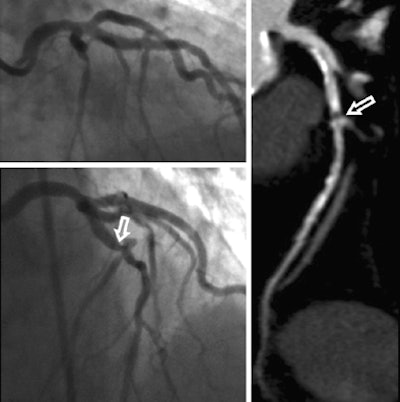

Invasive coronary angiography and coronary CTA studies in a 62-year-old woman. Significant stenosis of the mid left anterior descending coronary artery (arrows) just proximal to the second diagonal branch was missed during initial interpretation of invasive coronary angiograms (upper left) due to superimposition of vessels. The lesion was detected on coronary CTA, displayed as curved multiplanar reformat (right). Re-evaluation of invasive coronary angiography (lower left) after unblinding of coronary CTA results confirms lesion in a single angiographic projection. Images courtesy of Dr. Matt Kerl and Dr. U. Joseph Schoepf.On the other hand, 11 stenoses ≥ 50% in 11 patients seen at coronary CTA were not seen at the initial reading of angiography findings. After unblinding of CT findings, six of these stenoses were subsequently confirmed at angiography.